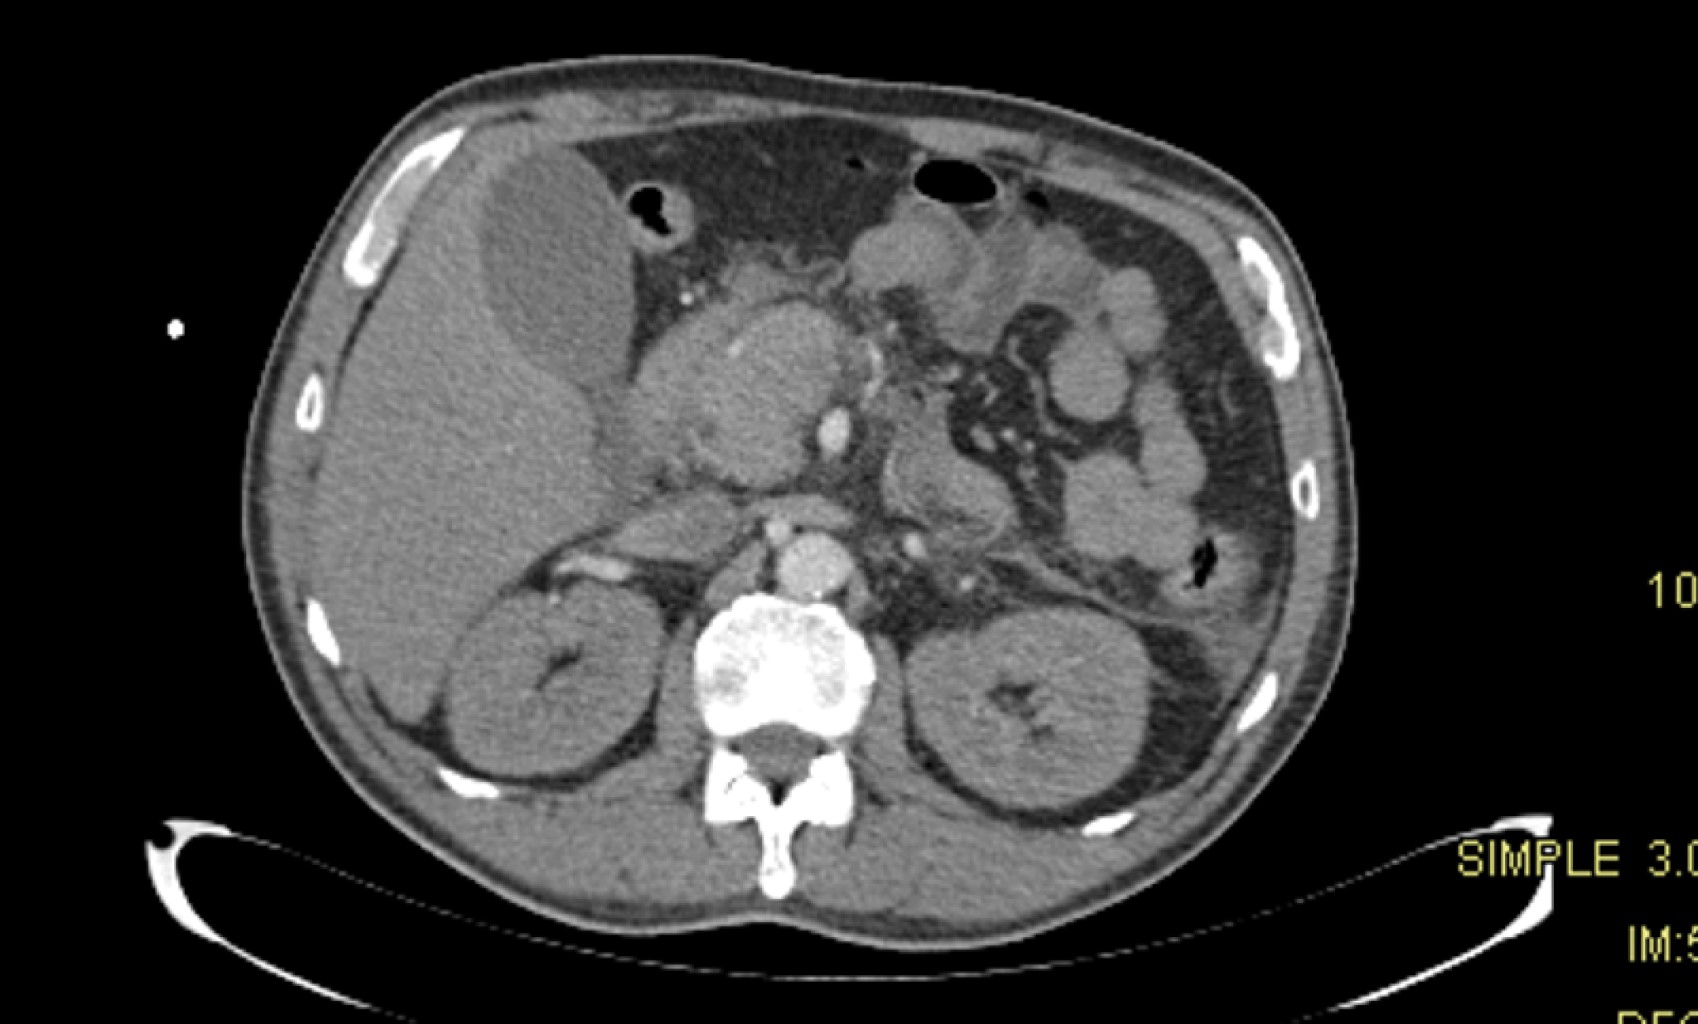

La evolución del paciente fue favorable al tratamiento médico de primera línea para el síndrome de Fisher-Evans, inmunoglobulina humana y esteroides (Figuras 2 y 3). Presentó mejoría de las cifras de hemoglobina, disminución de las cifras de bilirrubinas totales e incremento de la cuenta plaquetaria. Por último, fue egresado a domicilio con seguimiento en la consulta externa de nefrología y hematología. Se reportó por parte del servicio de nefrología recuperación de la función renal, con valores séricos de creatinina de 1.2 mg/dL.

Figura 2